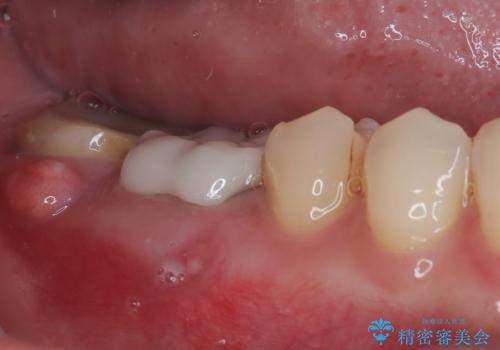

- 前歯に穴が空いてしまったとのことで来院された患者様です。

変色が気になっていたものの歯医者が怖くて来院を躊躇されていたそうです。

歯髄は既に壊死していたため、根管治療を行い、その後オールセラミッククラウンにて補綴することとしました。

審美障害が著しかったため、速やかに仮歯に置き換え、その後根管治療を行いました。根尖部の骨透過像が大きかったので、定期的にレントゲン写真を撮影し、1年後には有意に縮小していることが確認できました。